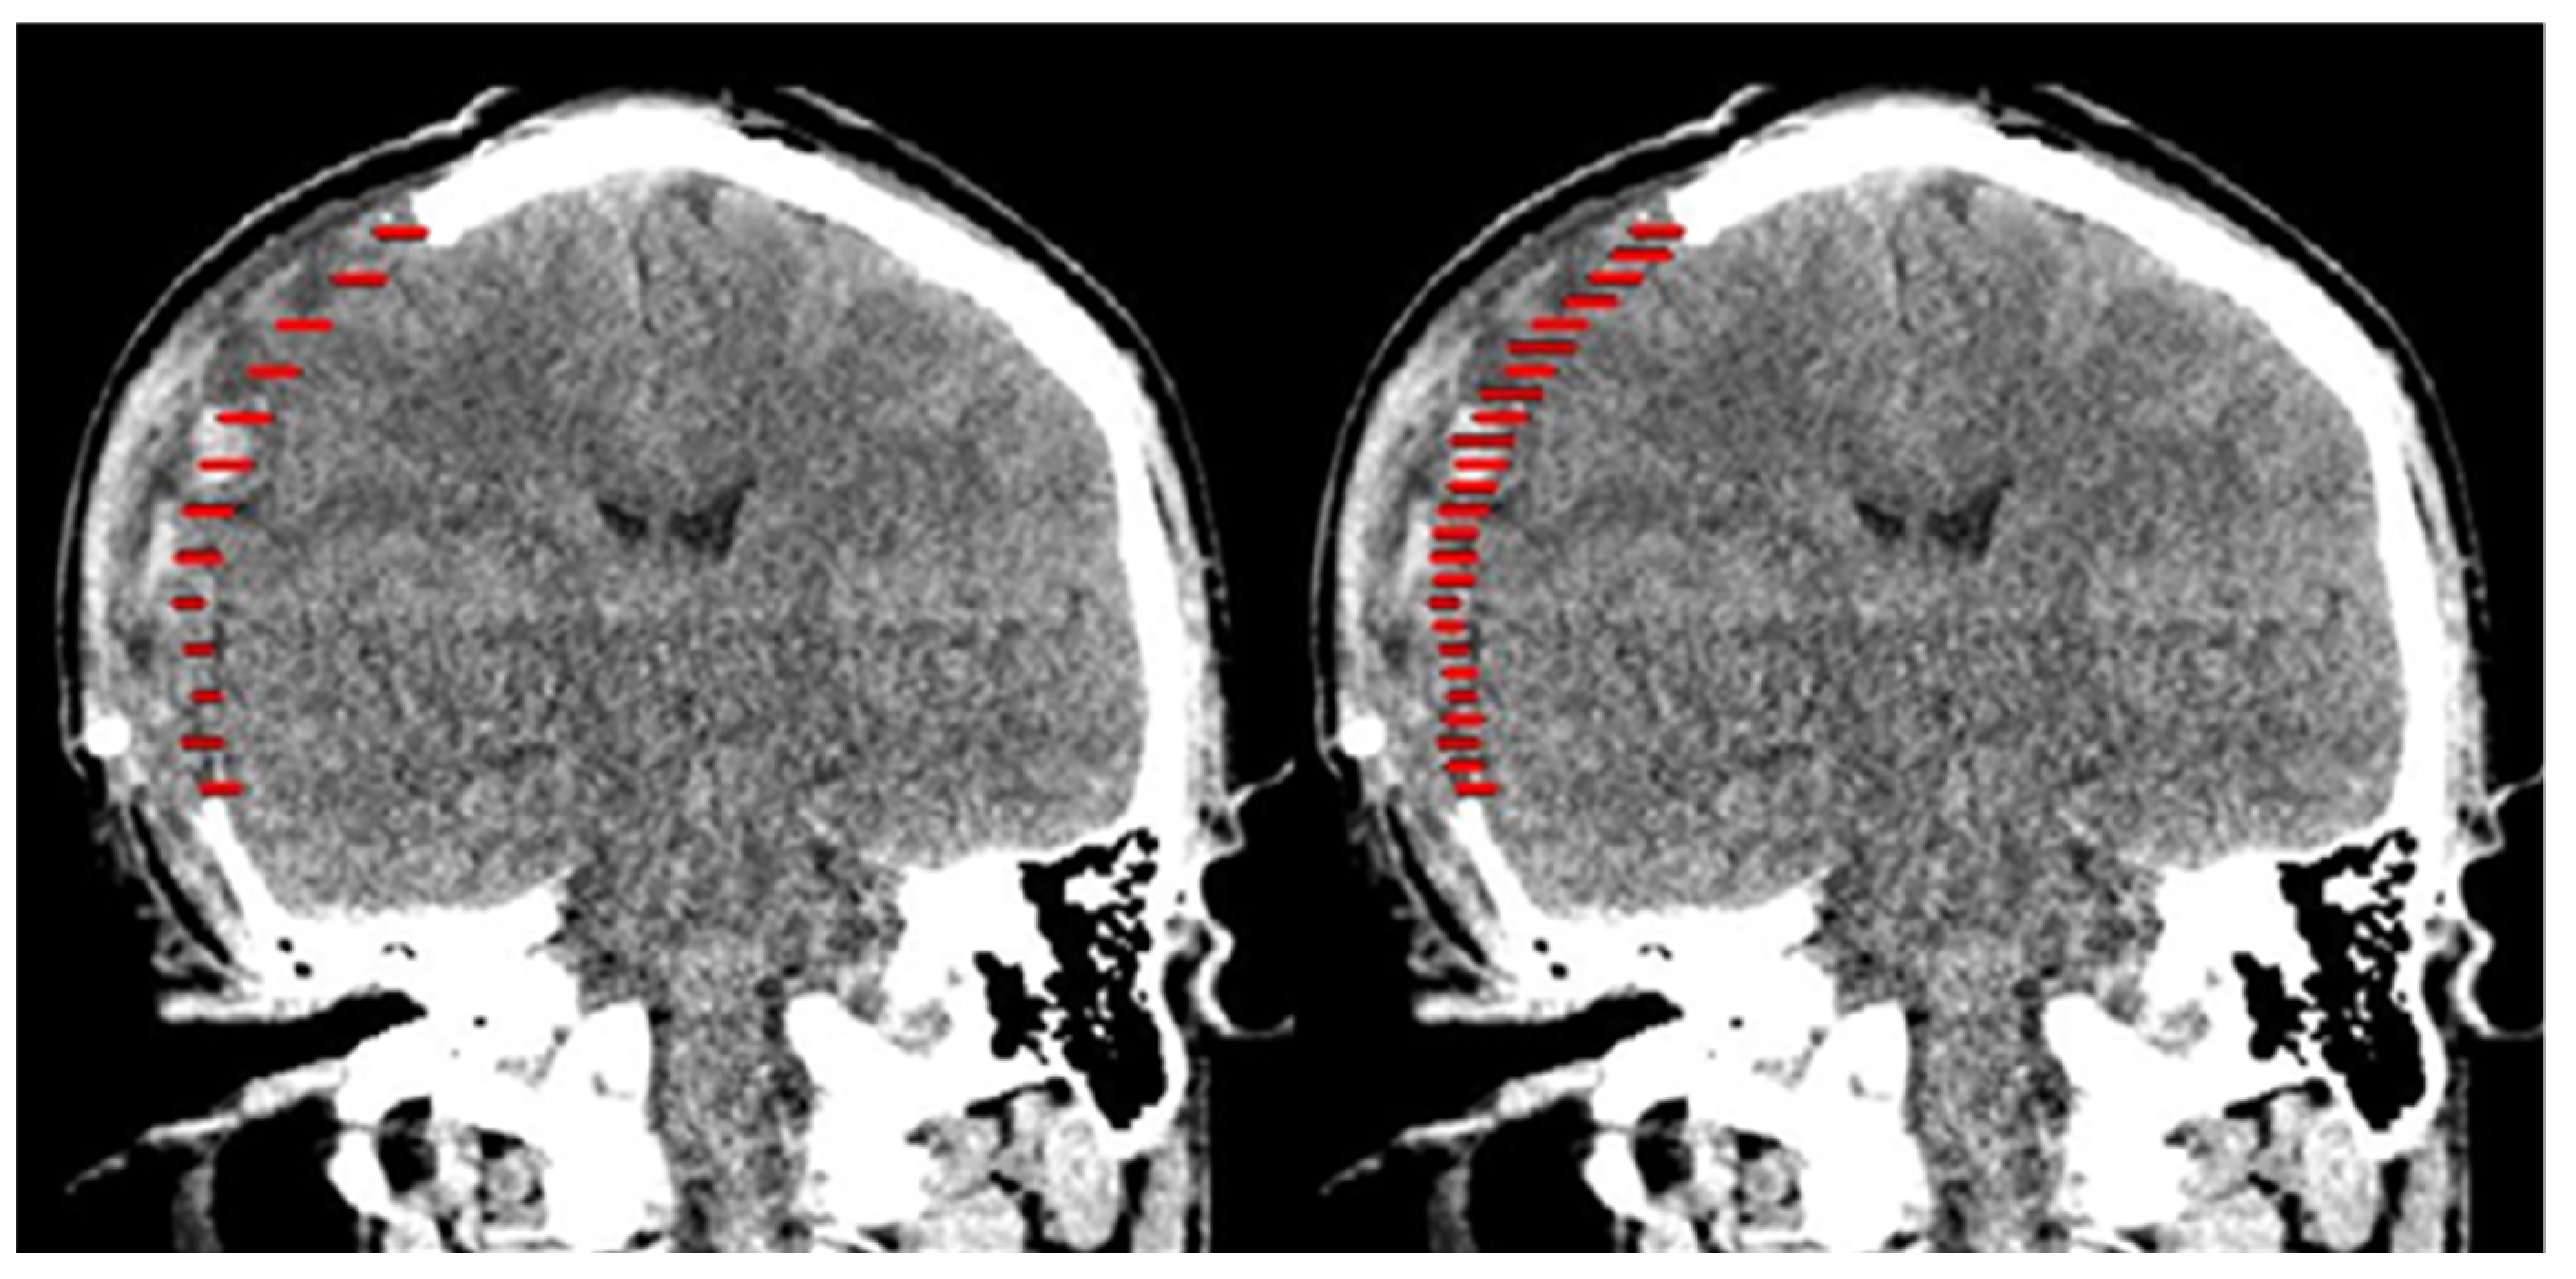

2.1. Design of Cranial Implants Using 3-Matic Software

2.2. Design of Cranial Implants Using MITK Software